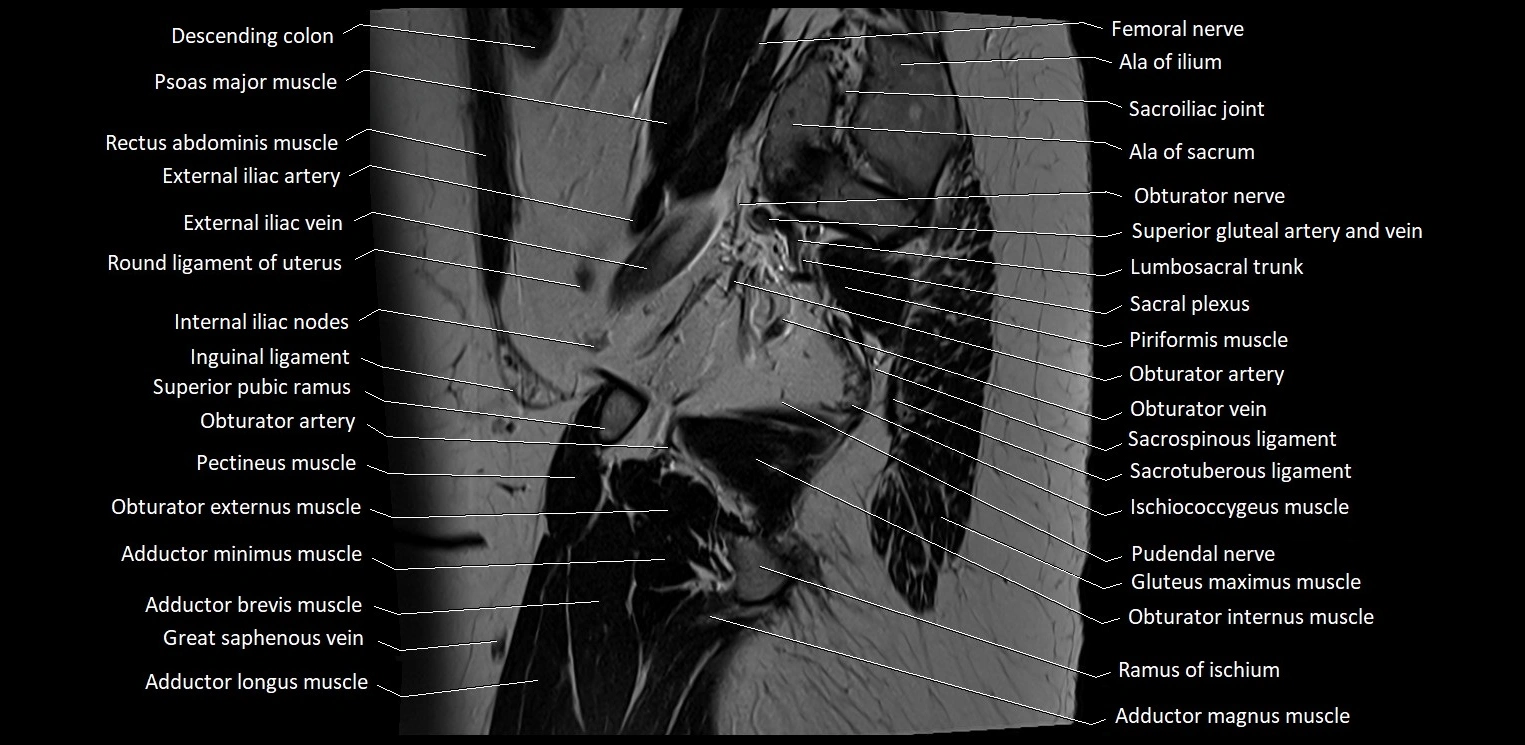

- Accessory obturator artery

- Accessory obturator vein

- Accessory saphenous vein

- Acetabular labrum

- Acetabular margin (Acetabular rim)

- Acetabular notch

- Acetabulum

- Adductor brevis muscle

- Adductor longus muscle

- Adductor magnus muscle

- Adductor minimus muscle

- Ala of ilium (wing of ilium)

- Ala of sacrum

- Anal canal